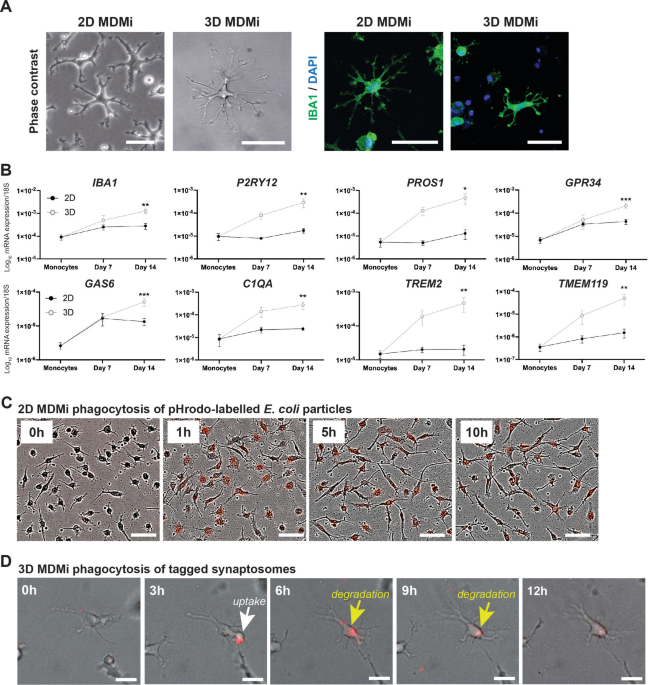

Fig. 2 shows an example of annotation indicating the extent of a colorectal tumor and its coordinates in a CT image used for the development of an AI algorithm. Data regarding the lesion location and size (i.e., circumscribed rectangle) were specified based on the colonoscopy findings and the correct number of lesions included in the CT colonography images used for training and validation. The annotation process and training were carried out by radiologists with experience in reading CT colonography; however no strict rules were imposed. The training and internal validation set were completely randomized during division. Lesions smaller than 6 mm were not assessed in this study.

Annotations for colorectal lesions. Annotation of the bounding rectangle surrounding the colorectal lesions known a priori to be correct on the CT image. CT: computed tomography.